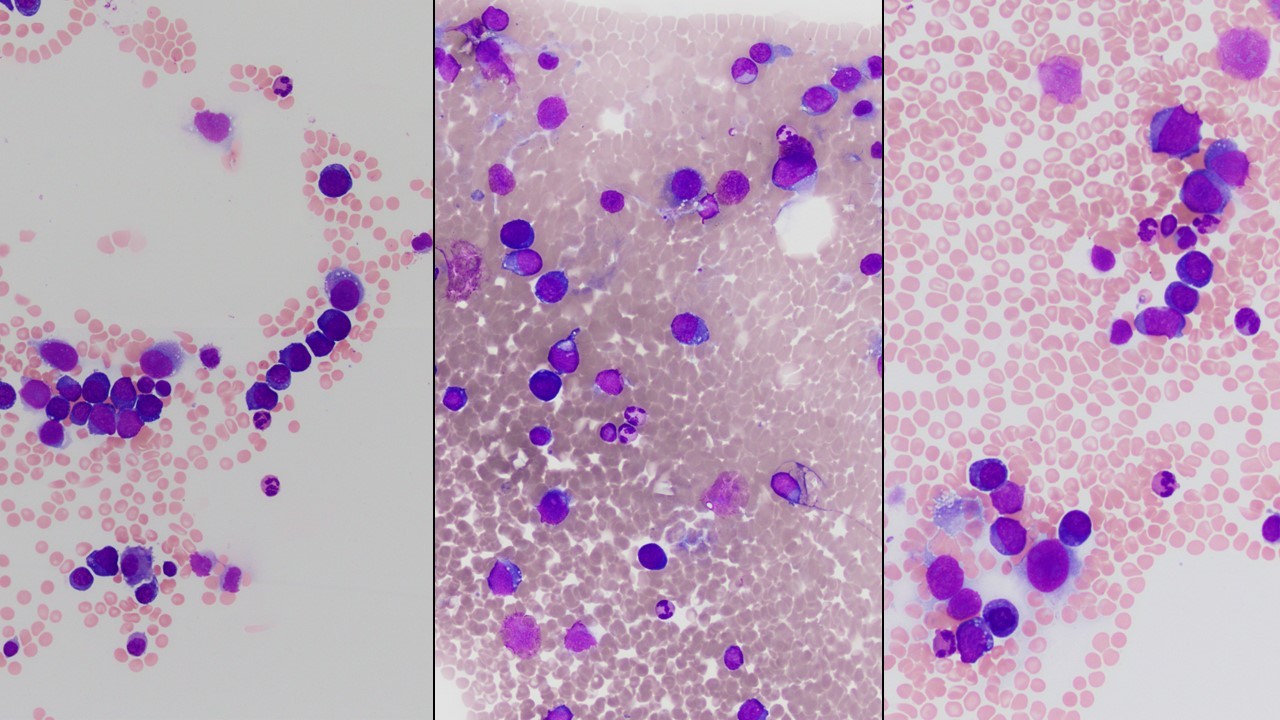

Megakaryoblasts are medium/large cells with dark blue vacuolated agranular cytoplasm. Cytoplasmic projections (blebs and pseudopods) resembling platelets, irregular cytoplasmic borders and cytoplasmic zoning maybe seen. Nuclei are round or slightly indented with finely reticular, dense chromatin and 1-3 nucleoli. Myelofibrosis or increased marrow reticulin is common fibrosis due to megakaryoblast secretion of fibrogenic cytokines, which makes marrow aspiration difficult.

Blasts are morphologically and immunophenotypically megakaryoblasts.

Marrow typically shows micromegakaryocytes without multilineage dysplasia.